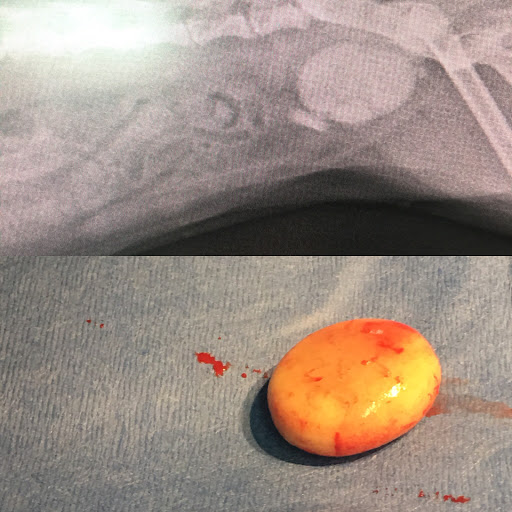

Photos

Photos of reviews